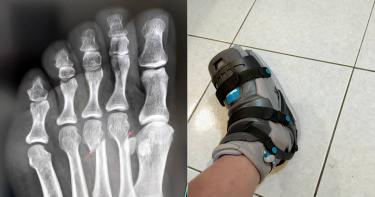

走路搖晃被誤會酒駕遭警攔下 女子秀「無敵鐵金剛腿」場面尷尬了

哭笑不得!一名女網友下班後開車去買晚餐,因為走路搖搖晃晃,被警方誤以為酒駕,她只好秀出「無敵鐵金剛」腳,經歷曝光後讓不少網友都心疼,掀起熱議。原PO在臉書「爆怨公社」提到,昨(29日)晚下班肚子有點餓,但又不想麻煩家人買餐,看到路邊有熱炒海產店,於是把車打閃燈臨停在黃線,並下車點餐,剛好前方紅線有2台違規的車輛,巡邏員警正在驅趕,當時她也剛好拿了餐,很認真想快步上車開走,但無法走太快,沒想到上車後警察過來敲車窗,要求查看證件。原PO道歉,自己是臨停拿晚餐,馬上就要開走了,「真的不好意思」,警察則表示是看到她走上車搖搖晃晃,認為她喝很多,並要求酒測,她強調自己沒喝酒,「我很守法的,而且我也不太喝酒」,但警察仍半信半疑,接著她打開車門,伸出左腳「無敵鐵金剛」,讓警察當場愣住。女網友左腳掌蹠骨斷掉,只能用腳後跟走路。(示意圖/翻攝自pexels)原PO解釋,她因為踩空掉落,左腳掌第3根蹠骨斷掉,只能暫時用後腳跟走路,至於被問腳受傷怎麼開車?她就用右腳開,因為還是必須出門,又不想什麼都麻煩別人,所以一切都很小心。臨走前,警察還不忘給她比個讚,叮嚀她要注意安全。原PO無奈表示,她也不想搖搖晃晃走路,希望可以盡快恢復,坦言當「企鵝」真的很難受,目前是受傷第7天,更直言骨頭斷掉的當下超級痛,比生小孩還痛。網友看到照片後,紛紛留言,「一定很痛,祝早日康復」、「警察大大跟妳比個讚的畫面感覺很暖心耶」、「真的,骨頭斷掉超痛的」、「要小心啊」、「都這樣還要上班,太拼了」。